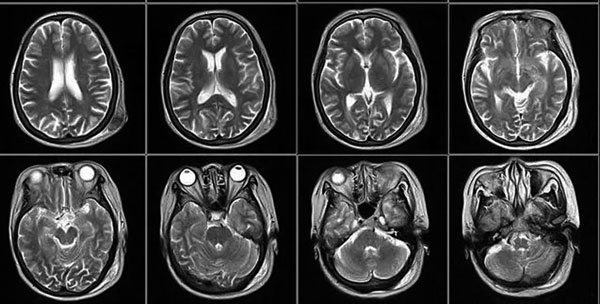

核磁共振摇一摇再看

核磁共振机使用较强大的磁场,使人体中所有水分子磁场的磁力线方向一致,这时磁共振机的磁场突然消失,身体中水分子的磁力线方向,突然恢复到原来随意排列的状态。简单说,就相当于用手摇一摇,让水分子振动起来,再平静下来,感受一下里面的振动。所以,核磁共振也被戏说为是摇摇看的检查。

2、颈椎腰椎——最佳选核磁,次选CT

颈椎病、腰椎间盘突出等椎间盘疾病需要观察椎间盘与相应的神经根,要想更好观察这些软组织,最优选择就是核磁。同样,对于关节、肌肉、脂肪组织检查,核磁也是首选。

5、心脏——排除冠心病用CT,看心功能用超声

常规的心脏结构与功能检查,心脏彩超所提供的信息已经较为充分,又简单易行。

用CT可检查冠状动脉,但冠脉CT检查辐射量较大,不适合作为常规体检。核磁虽无电磁辐射,但对冠状动脉的观察不及CT。心脏核磁则是评价心脏结构和功能的"金标准"。